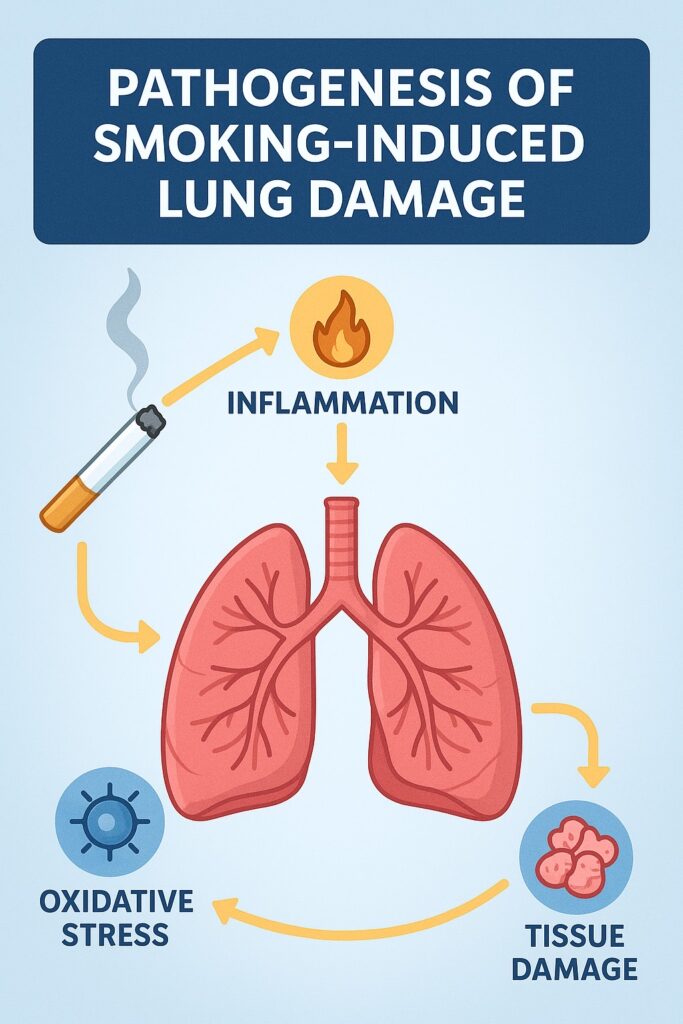

| ปอด (ระยะยาว) | เสี่ยงต่อโรค “ปอดอักเสบจากสารเคมี” (Chemical pneumonitis) |

| ปอด | กลีเซอรีนเมื่อถูกทำให้ร้อนอาจเปลี่ยนเป็นสารพิษ เช่น อะโครลีน (Acrolein) ทำลายเนื้อเยื่อปอด |

| ระบบภูมิคุ้มกัน | ลดการตอบสนองภูมิคุ้มกันในเซลล์ปอด |

แม้ไม่ได้เติมโดยตรง แต่น้ำยาบุหรี่ไฟฟ้าเมื่อถูกความร้อน อาจสร้าง สารพิษ ได้ เช่น:

| Formaldehyde | การเผาไหม้ของ PG/VG ที่อุณหภูมิสูง | สารก่อมะเร็งระดับ 1 |

| Acrolein | ผลจากการสลายของกลีเซอรีน | ทำลายปอด, หลอดลมอักเสบ |

แม้จะไม่มีควันและกลิ่นเหมือนบุหรี่ธรรมดา แต่น้ำยาบุหรี่ไฟฟ้าประกอบด้วย สารเคมีที่เป็นอันตรายต่อร่างกาย โดยเฉพาะเมื่อ:

- สูดดมเข้าไปในระยะยาว

- ใช้ในวัยรุ่น เด็กเล็ก หรือหญิงตั้งครรภ์

- ใช้ของปลอม น้ำยาไม่ได้มาตรฐาน หรือดัดแปลงเอง